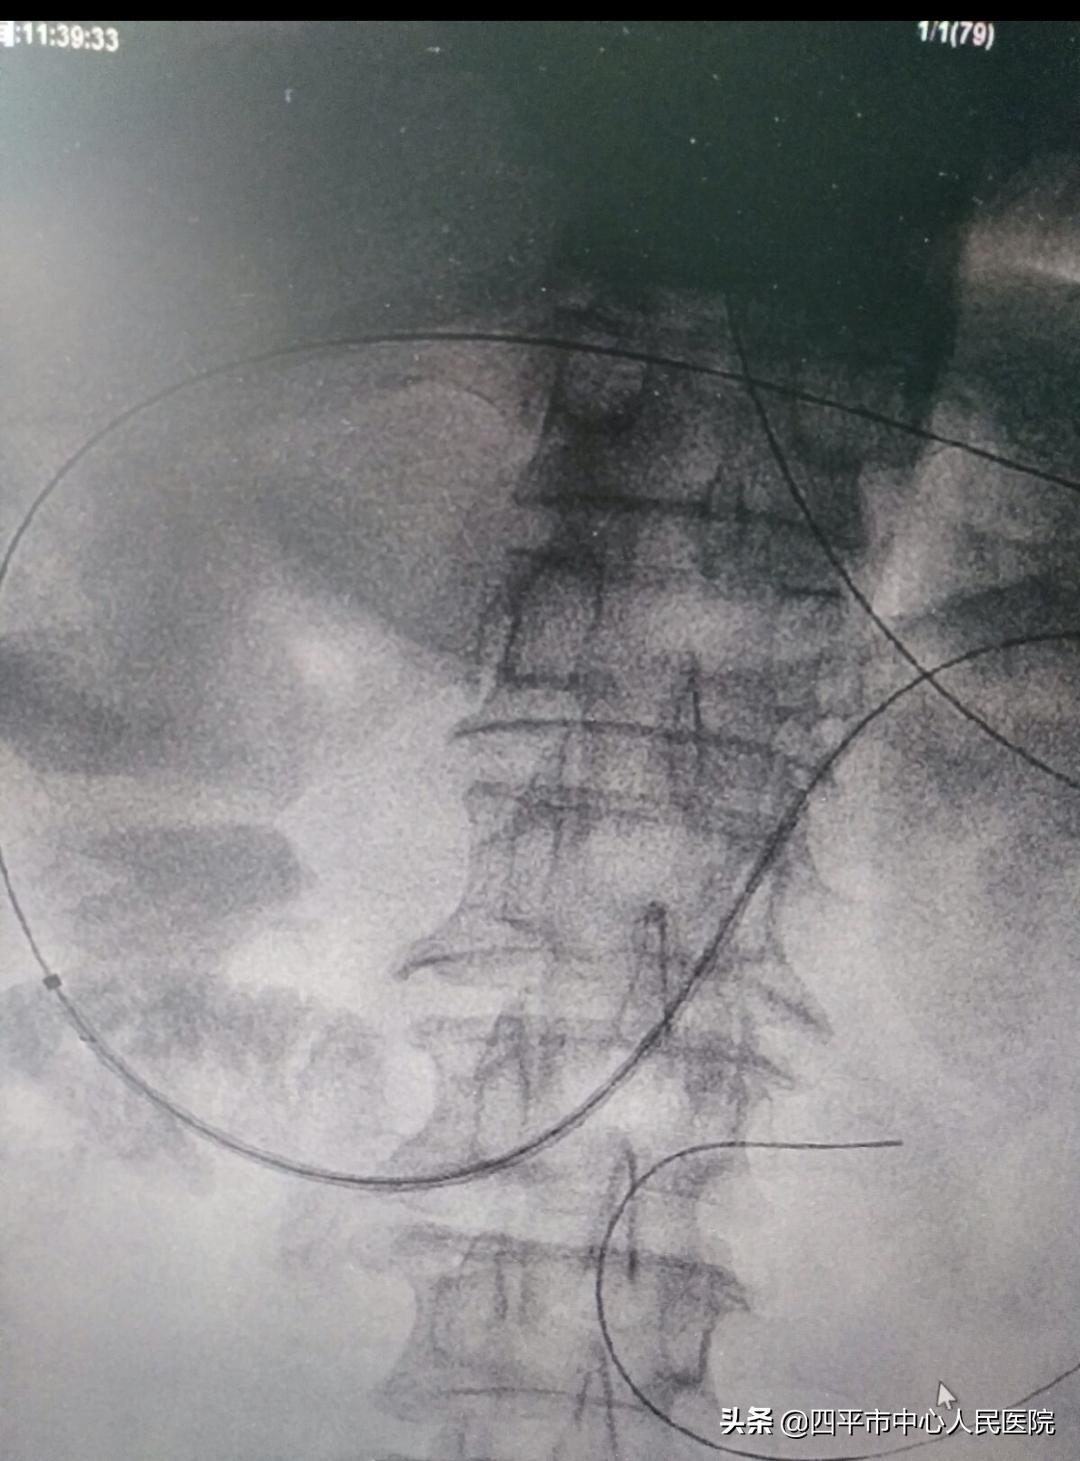

DSA下造影透视显示造影剂通过不畅

置入导丝通过十二指肠狭窄部位后引入十二指肠支架